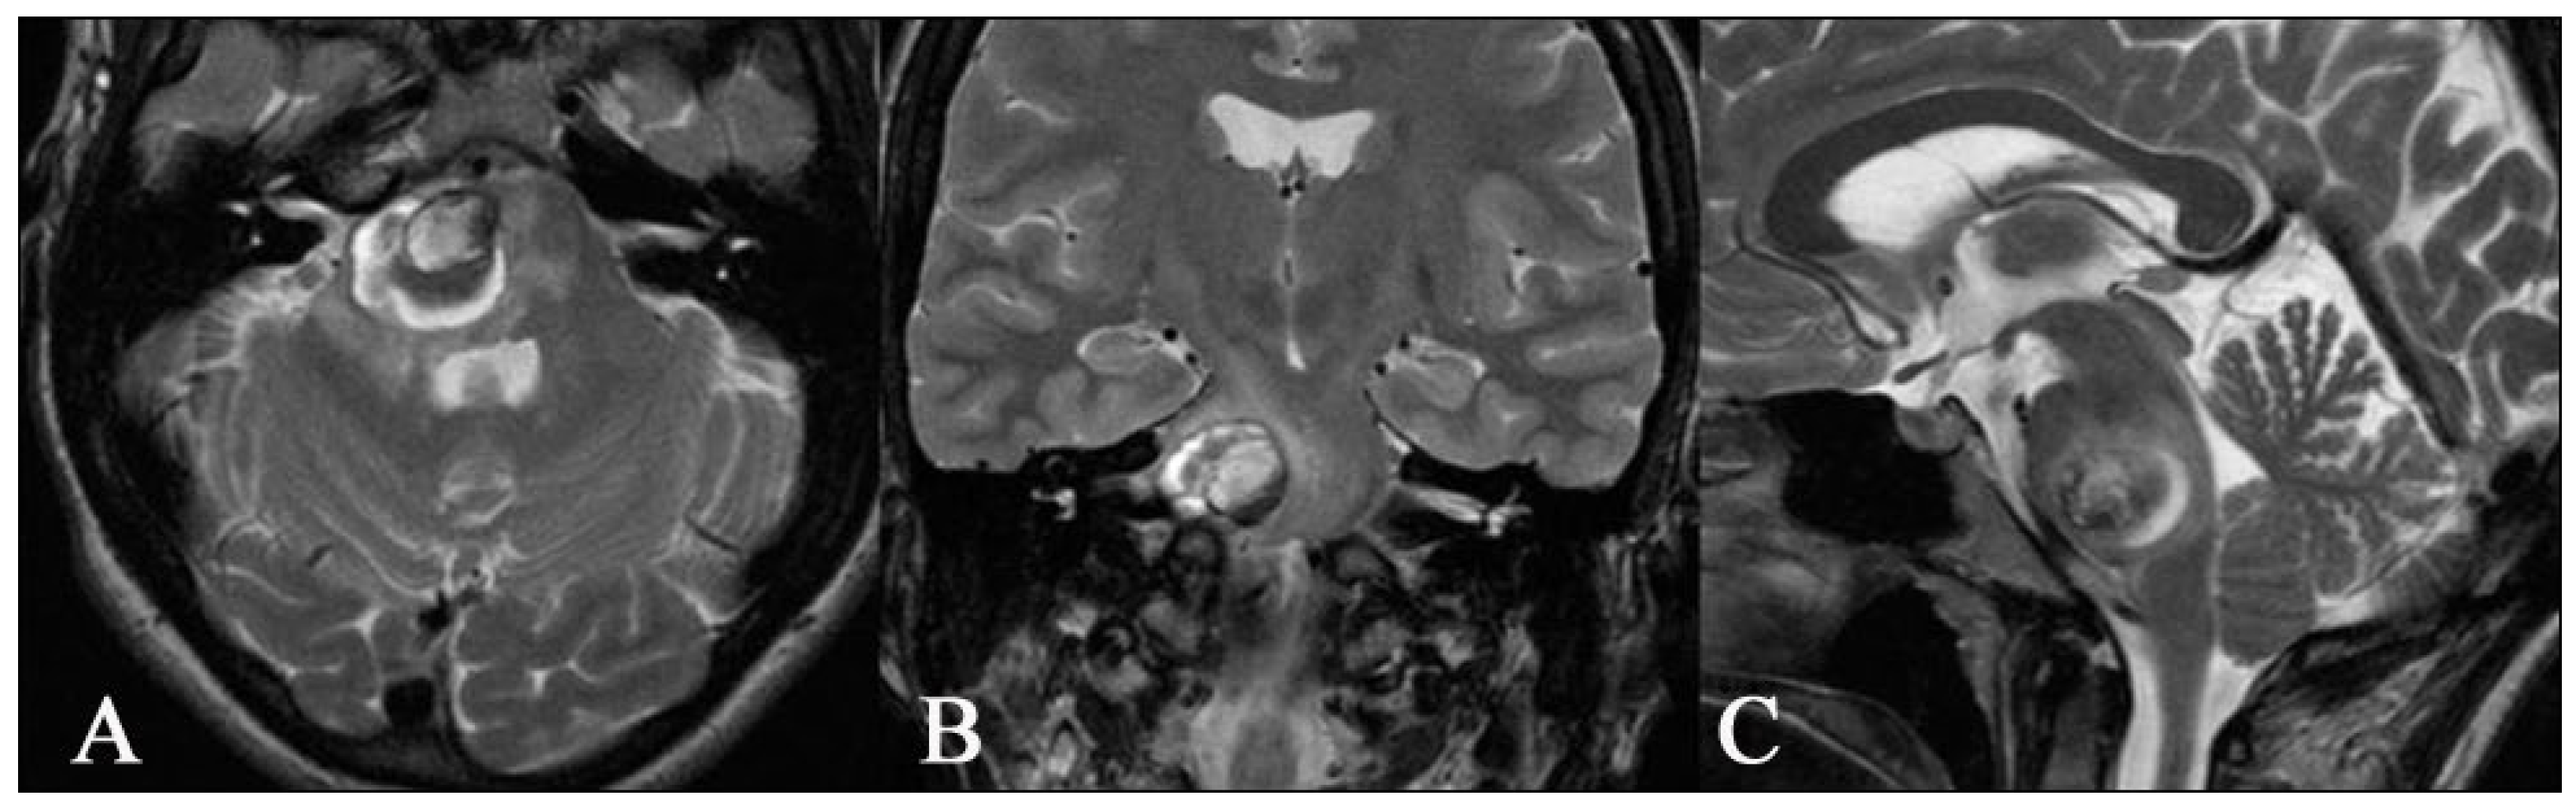

Figure 7. Preoperative axial (A), coronal (B), and sagittal (C) T2 images MR of a 35-year-old woman showing a superficial cavernoma in the pons on the right side. The patient suffered from headaches and gait disturbances for several weeks.

Figure 8. Postoperative axial (A), coronal (B), and sagittal (C) T1 images MR with contrast enhancement showing that complete removal of the superficial cavernous malformation of the pons was achieved. In the coronal image in the centre, the microsurgical entry site into the brainstem can be seen (white arrow). After surgery, no new neurologic deficits occurred in the immediate postoperative period or during the 3-month follow-up.